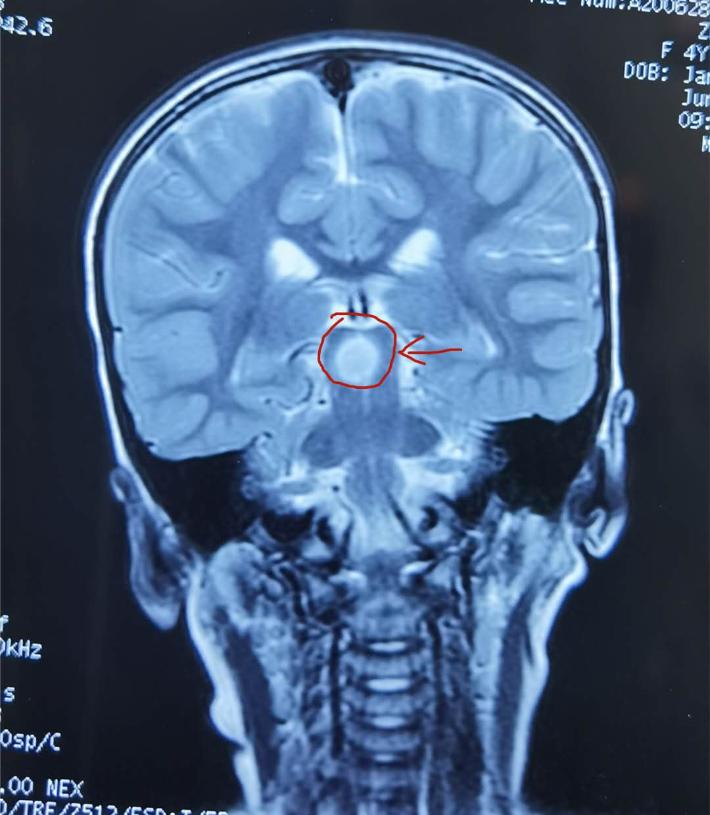

术前冠状位

术前轴位